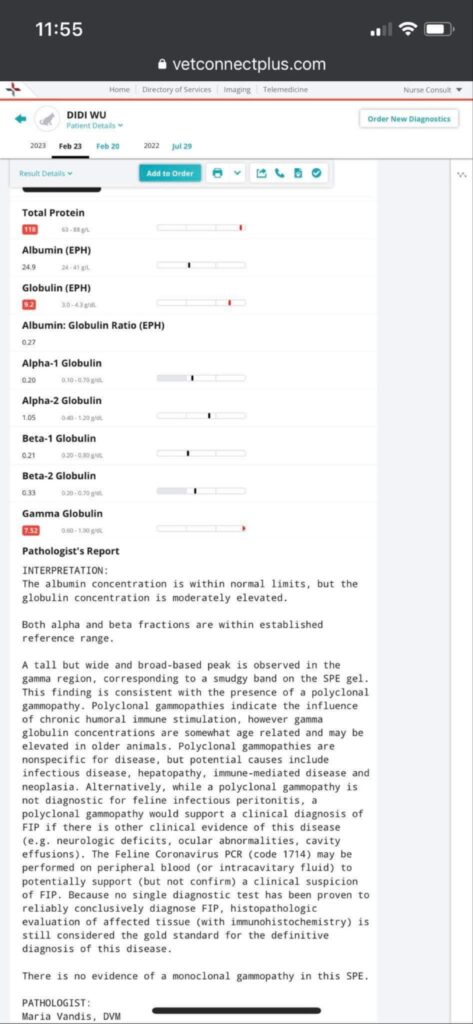

Noon: dr d “Polyclonal for didi, so no clear tumor suspect. This happens in chronic inflammation, either viral bacterial or parasitic. Or immune mediated. but very unlikely the tumor we thought…. myeloma would not look like this. so can almost 95% rule out. or try investigate lot further, maybe try to get sample from the enlarged liver or lymf nodes. lot more invasive. have you given him an antibiotic trial at some point already? dewormer?” – reminded dr d that didi alr on Clav jab 0.19ml